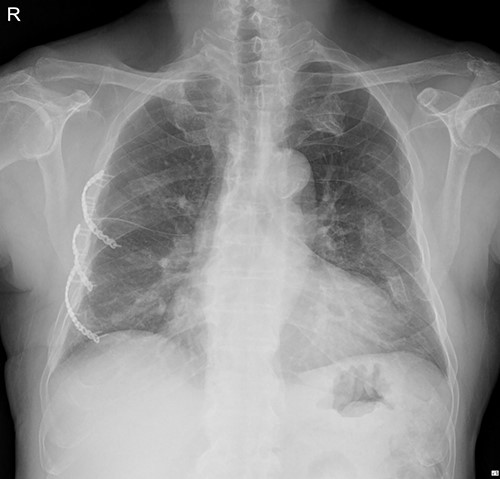

The patient underwent plate removal surgery on 24 February 2022. The operation was performed routinely. Under general anesthesia, a small incision was made on the previous operation scar. After sufficiently dissecting surrounding tissues and muscles, we skimmed implants off the rib cage. Then, a seven-French sizes (FR) drainage catheter was placed below the serratus anterior muscle (SAM) to manage potential minor complications. Because we usually do not invade the rib cage during plate removal operations, there was no need to be concerned about lung injury. The patient was discharged on hospital Day 2 with the submuscular drainage catheter removed (Fig. 2.).

Immediate postoperative chest X-ray after plates removal (24 February 2022).